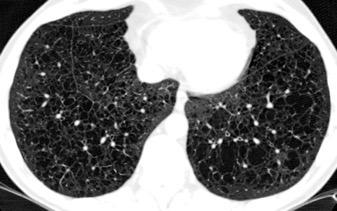

< Volumen pulmonar

Síndrome antisintetasa

(Miositis anti Jo-1).

Artralgias migratorias, Miositis, “Manos de mecánico”, Raynaud y Enfermedad

intersticial pulmonar (>70%).

Waseda Y et al.. Eur J Radiol. 2016